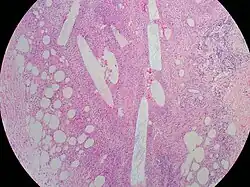

Excisional biopsy involves surgically removing the suspicious area of the breast to examine it under the microscope for diagnosis. One method is wire-guided (or wire-localized) excisional biopsy, where a wire is inserted into the breast and repeatedly imaged using breast ultrasound or mammography until the technician sees that the tip is located in the suspicious area. The suspicious area is then removed entirely in one block by the surgeon with the help of the wire.[10][20] When the tissue is removed, it is processed by a pathologist, who describes the tissue as it appears by eye and inks the sides to help orient the tissue under the microscope after it is sliced.[10] Each color corresponds to a direction, such as superior, inferior, medial, lateral, anterior, and posterior (these correspond to top, bottom, outside, inside, front, and back).[10] When the tissue is then looked at under the microscope, the margins can be evaluated to see if they are free of cancer cells, or if the surgeon needs to go back and remove more tissue from that area.[10] Titanium surgical clips are often left behind by surgeons to help future physicians locate the site and monitor for future disease or target the area with radiation if needed.[10] Percutaneous ("through the skin") biopsy methods have become more favored over surgical biopsies due to the high rate of benign findings (80%) and the reduction of adverse effects such as scarring.[11]